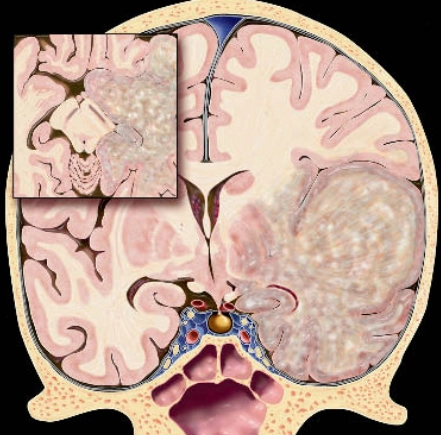

U nguyên tủy bào (Medulloblastoma)